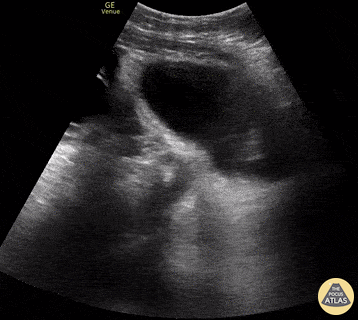

20 y/o female s/p egg retrieval for egg donation 3 days prior presents for diffuse abdominal pain and bloating. In the clip (bladder sagittal view), you can see massive enlargement of the ovary and its multiple follicles. FAST revealed free fluid throughout the abdomen likely secondary to leakage of fluid from these follicles, a process referred to as ovarian hyperstimulation syndrome (OHSS). The patient was admitted to GYN for possible drainage. Jennifer Kaminsky, MD PGY-2; @jen_kaminskyMD Pamela Santivanez, MD PGY-1 Sean Beckman, Rocky Vista University COM OMS-4 Joshua Greenstein, MD, Director of ED Ultrasound Northwell Health - Staten Island University Hospital